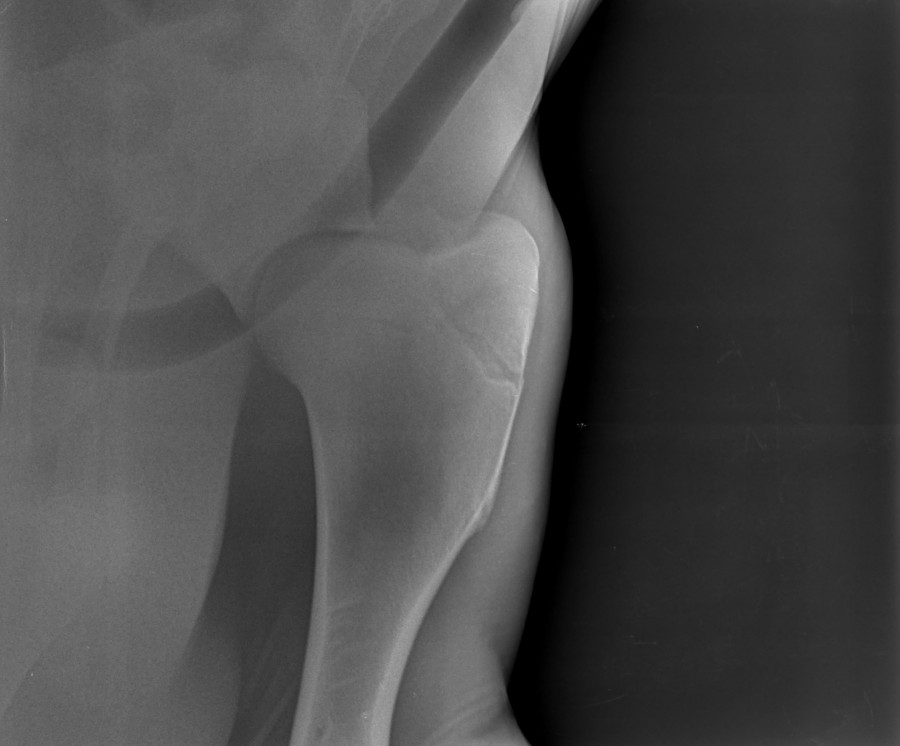

Salut, j'ai eu les radios de granola avec du retard !

mardi aprem radios de contrôle !